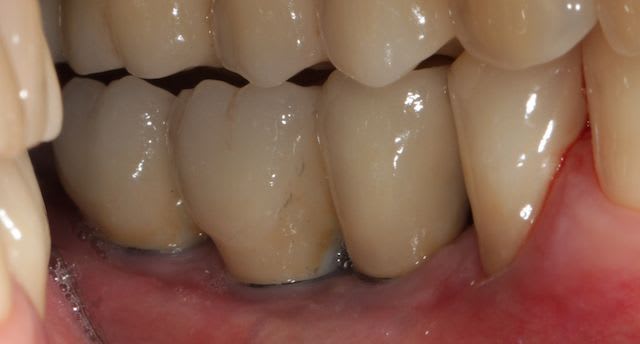

Bon ben voilà c'est fini, reste plus qu'a faire l'autre coté ;)

Img 4431 so0uck - Eugenol

Img 4427 vd1sxf - Eugenol

Versini gs7unb - Eugenol

Img 4430 pddcyk - Eugenol

Photo 158 mluhia - Eugenol